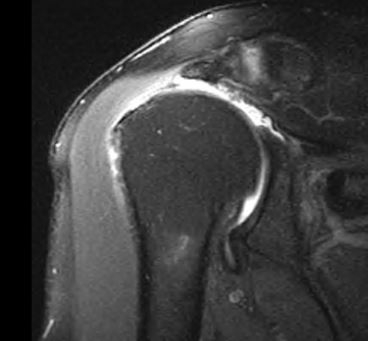

Irreparable Rotator Cuff Tear